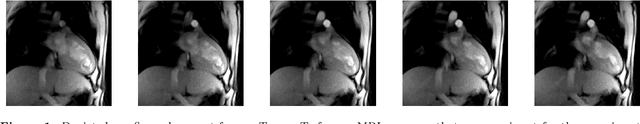

Abstract:While deep learning has achieved significant advances in accuracy for medical image segmentation, its benefits for deformable image registration have so far remained limited to reduced computation times. Previous work has either focused on replacing the iterative optimization of distance and smoothness terms with CNN-layers or using supervised approaches driven by labels. Our method is the first to combine the complementary strengths of global semantic information (represented by segmentation labels) and local distance metrics that help align surrounding structures. We demonstrate significant higher Dice scores (of 86.5\%) for deformable cardiac image registration compared to classic registration (79.0\%) as well as label-driven deep learning frameworks (83.4\%).